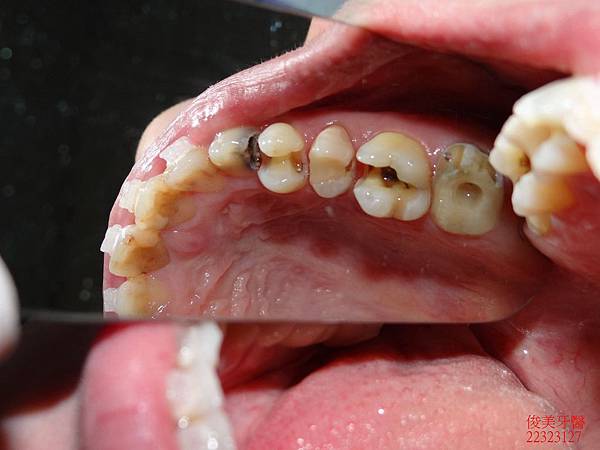

側邊咬合。

上排牙齒已有延長的現象,牙縫更容易塞東西,且沒有咀嚼功能。

蛀牙過多,且深。牙弓形狀已非標準形態。

咬合調整完成,開始處理患者的蛀牙。先移除舊的填補物....